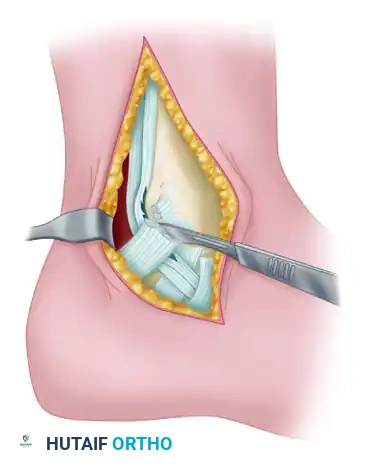

- Retinaculum Release: Release the pulley behind the medial malleolus (the flexor retinaculum or laciniate ligament) and the deep investing fascia of the distal leg.

- Debridement: By sharp dissection, meticulously remove all abnormal-appearing, hypertrophic synovium.

FIGURE 82-20 Abundant synovium surrounding the posterior tibial tendon. This extended from the inferior edge of the flexor retinaculum to the tuberosity of the navicular. Evaluation for rheumatoid arthritis and seronegative spondyloarthropathy was negative. The patient was a large-framed man with mild unilateral pes planus and posterior tibial insufficiency secondary to tenosynovitis and loss of tendon excursion through the pulley of the flexor retinaculum.

Tendon Inspection and Repair

- Inspection: Thoroughly inspect the tendon for longitudinal tears, myxoid degeneration, and intratendinous fibrosis.

- Distal Evaluation: Trace the plantar slip of the tendon 1 cm distal to the navicular tuberosity to be absolutely certain it is intact and functional.

- Imbrication: If the tendon insertion into the navicular and the slip plantar to it appear intact, but the tendon is attenuated or exhibits longitudinal splitting, imbricate the tendon across the abnormal-appearing area.

- Excision of the degenerative intrasubstance tissue is performed first.

- The imbrication (often a side-to-side tubularization or a pants-over-vest repair using non-absorbable suture) is performed over a length of 1.0 to 1.5 cm to restore appropriate tension and structural integrity.

- Closure: Leave the flexor retinaculum open to prevent postoperative stenosis and ischemia of the tendon. Close the subcutaneous tissue and skin in a standard layered fashion.

Surgical exposure demonstrating the posterior tibial tendon after release of the flexor retinaculum and excision of the tendon sheath.